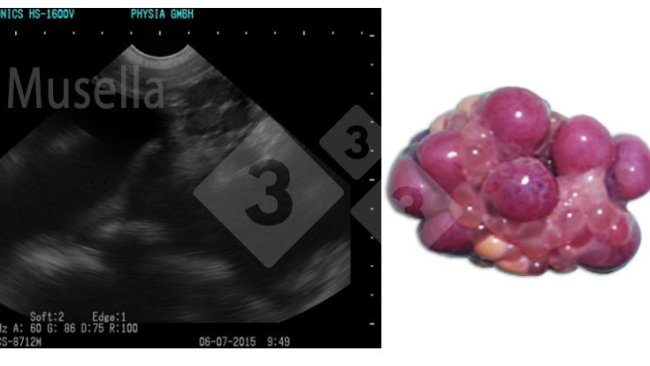

O ultrassom pode ser usado para visualizar as estruturas ovarianas, avaliar o estado puberal e diagnosticar patologias ovarianas.